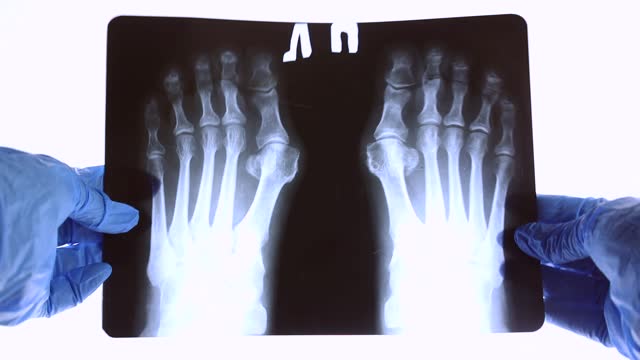

무지 외반증의 심각한 경우에는 전문가 상담을 고려해야 합니다. 물리치료사나 발건강 전문가와 상담하여 적절한 치료 방법을 찾아보세요.